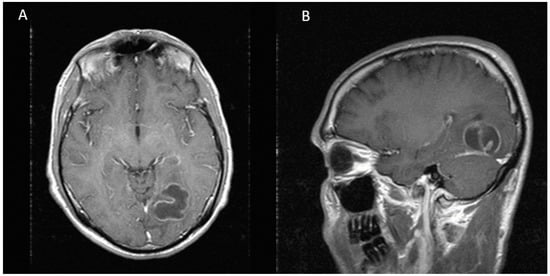

Figure 3.

Eight months after second stereotactic needle aspiration, MRI is showing a complete resolution of cerebral abscess. (A) Axial view (B) Sagittal view.